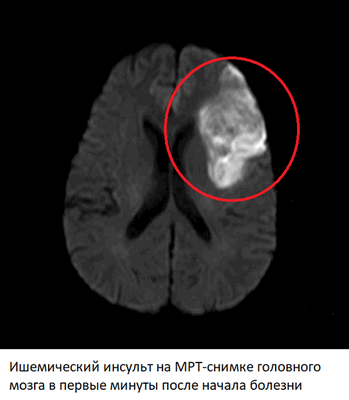

Признаки ишемического инсульта на МРТ головного мозга

В первые минуты после закупорки сосуда прекращение поступления крови к тканям головного мозга приводит к ишемии или недостатку кислорода и питательных веществ. Если сосуд был перекрыт не полностью, и какая-то часть крови продолжает поступать, ишемия может сохраняться в течении нескольких часов или даже дней - такое состояние называют транзиторной ишемической атакой. Однако если тромб перекрыл артерию полностью, уже через 5-10 минут ишемия приводит к гибели нервных клеток и некрозу тканей мозга - необратимому состоянию.

Изменения на МРТ после ишемического инсульта - в стандартных режимах на снимках отсутствуют явные изменения, однако в некоторых режимах (DWI, ADC) уже через несколько минут после начала инсульта видны четкие признаки ишемии и некроза. В ангио-режиме можно обнаружить тромб, вызывавший закупорку артерии, определить его расположение, протяженность, от которых будет зависеть прогноз.

Через 6 часов после начала острого нарушения мозгового кровообращения по ишемическому инсульту начинают появляться структурные изменения, видные и в других режимах МРТ (FLAIR, T2). Оборудование “видит” участок мозга, подвергшийся некрозу, из-за отека тканей. Такая картина сохраняется на протяжении 1-2 недель. Через 3 недели картина начинает приходить в норму, однако отмерший участок мозга никогда не будет прежним, что частично видно на снимках вне зависимости от того, сколько времени прошло. Если некроз возник в зонах мозга, отвечающих за речь, слух, зрение, двигательную активность, восстановление соответствующих функций может занять месяцы и годы или же не произойти никогда.